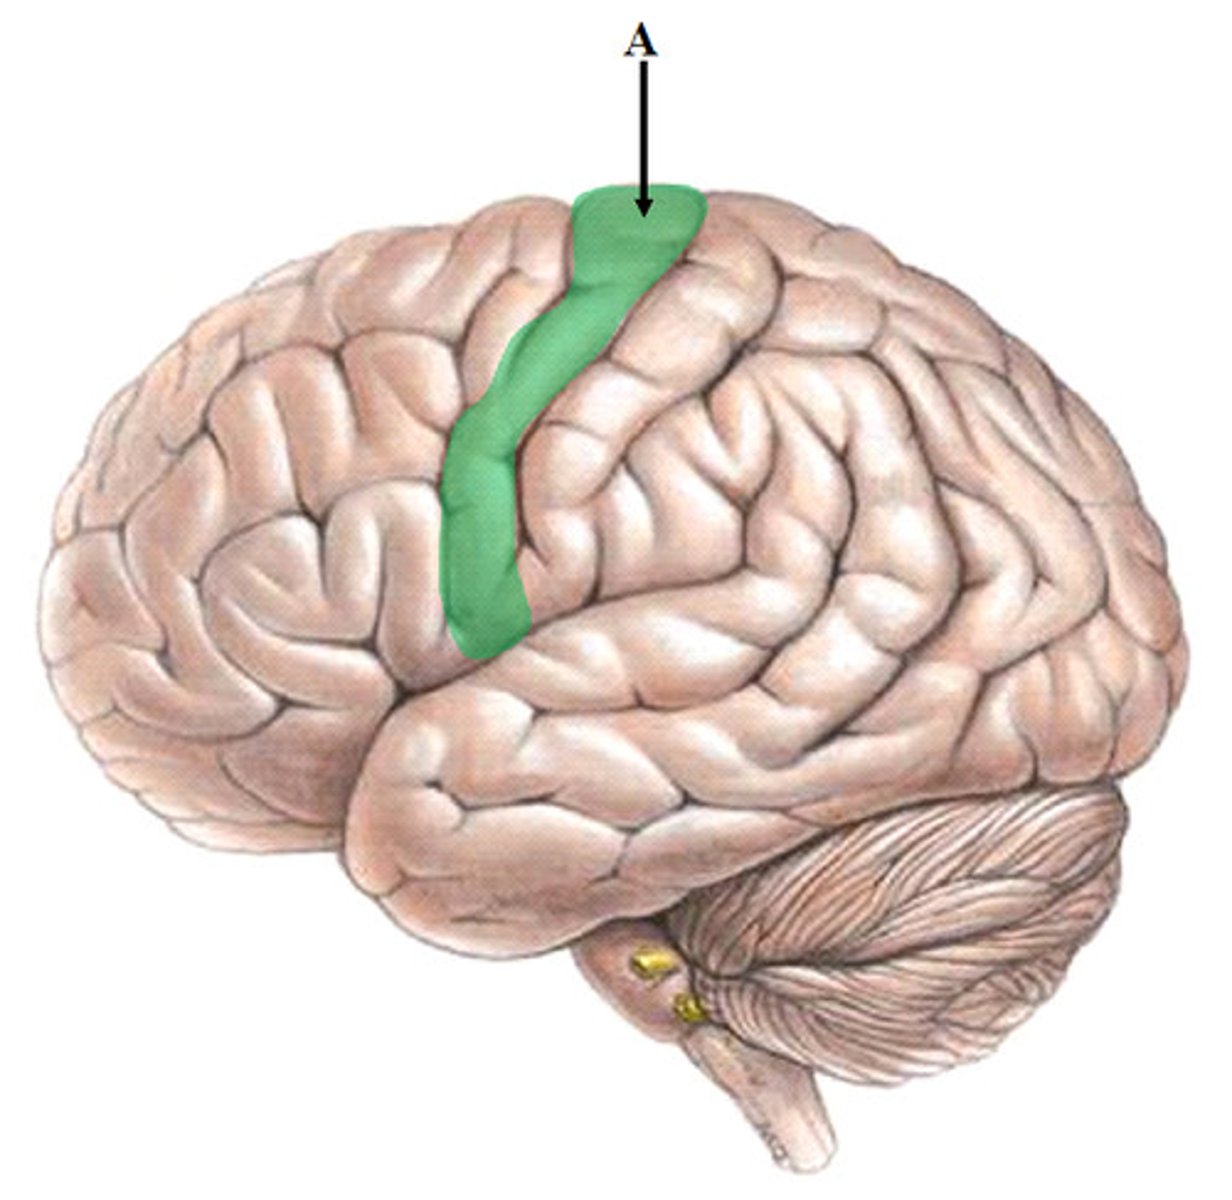

postcentral gyrus

primary somatosensory cortex

central sulcus

between postcentral and precentral gyri

A region of the cerebral cortex whose functions include processing information about touch, contains primary somatosensory cortex